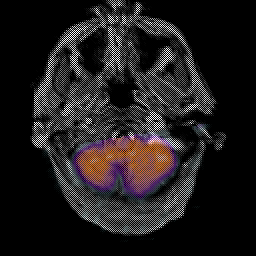

Glioma Overlay -- Slice #2

Click on sagittal image to select slice. Click on thin tickmark to change timepoint, or thick tickmark for overlay.